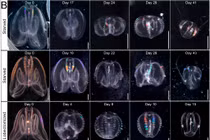

![]() |

| Ảnh minh họa. |